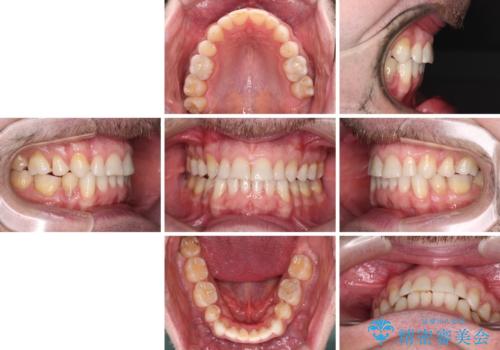

- 上下前歯の叢生を気にして来院された患者様です。

抜歯矯正をした後戻りということで、歯列不正はそれほど大きくなかったため、インビザライン・ライトを用いて矯正治療を行うこととしました。

前歯のデコボコが残っており、シミュレーション通りに動いていない部分がありましたが、再矯正であることやご本人の満足いくところまでデコボコが改善されたとのことで、治療を終了することとしました。